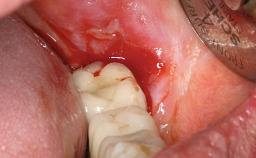

In this video Dr. Legg will demonstrate the process of utilising fully guided surgery as well as reconstruction to provide immediate full arch rehabilitation. A 56-year-old female with chronic adult periodontitis had previously undergone significant nonsurgical periodontal therapy. Unfortunately she had reached the stage where she was no longer happy with the appearance of her teeth and was suffering from increasing discomfort. A full workup was carried out in conjunction with a technical design team (at Createch). This included digital wax up of the proposed teeth, digital placement of the proposed implants and the design of the requisite surgical guides. The surgery was then carried out under sedation. The remaining upper teeth were removed, bone reduced where appropriate and the implants placed using a fully guided protocol. Following placement of screw retained abutments, the immediate provisional prosthesis was picked up in situ and passed to the technician for finishing before being fitted.

Radicular morphology Multi-radicular/divergent roots - available interseptal bone

Socket walls Intact

Thickness of buccal wall less than 2 mm

Inter-radicular bone (multi-rooted teeth) Wide - allowing drilling and implant anchorage

Anticipated residual defect after implant placement 2 mm or less